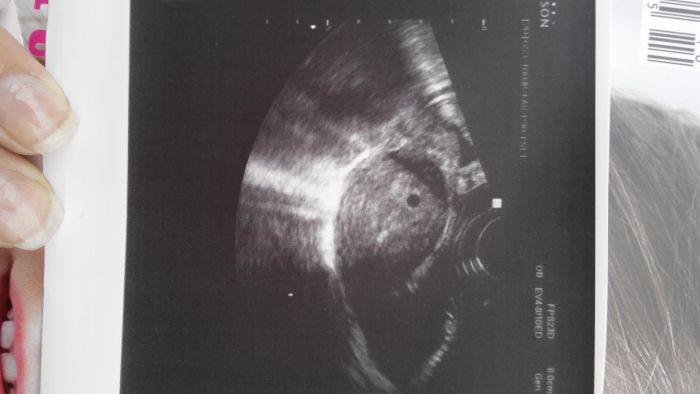

Lucy, dneska me zacali pekne bolet prsa, jinak na zveaceni mi uz neni, ani brisko me neboli. A tady drobeckova prvni fotka :) mam v ocich slzy :)

[659070] Ahoj Mony, a kolik ti přesně řekl, že jsi tt+den? :-) Fotečka krááásnáááá

to je gestační váček, nebo žloutkový? No mě není dneska absolutně nic

Holky, nevim co to je :D je to koralek :D na dalsi kontrolu jdu za 14 dni, dostanu teh.kartu. nerekl mi zatim nic :) drzim vam palce holky aby ste meli taky takovouhle fotecku. Jinak sem dneska zjistila, ze parky ne-e :D